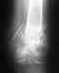

Сестра попала в ДТП, в результате которого получила сложный перелом плечевой кости правой руки.

рука была про оперирована, вставлена пластина, предположение о повреждении нерва не подтвердилось, он был просто пережат. Сейчас прошел уже месяц после операции, сестра руку разрабатывает пока самостоятельно. результаты небольшие, но есть. хотела проконсультироваться о прогнозах, т.к. после выписки из больницы и придя на осмотр к травматологу по месту жительства, местный врач предложил ей оформить инвалидность, т.к. по его мнению рука работать уже не будет. К кому можно обратиться за консультацией по этому вопросу?